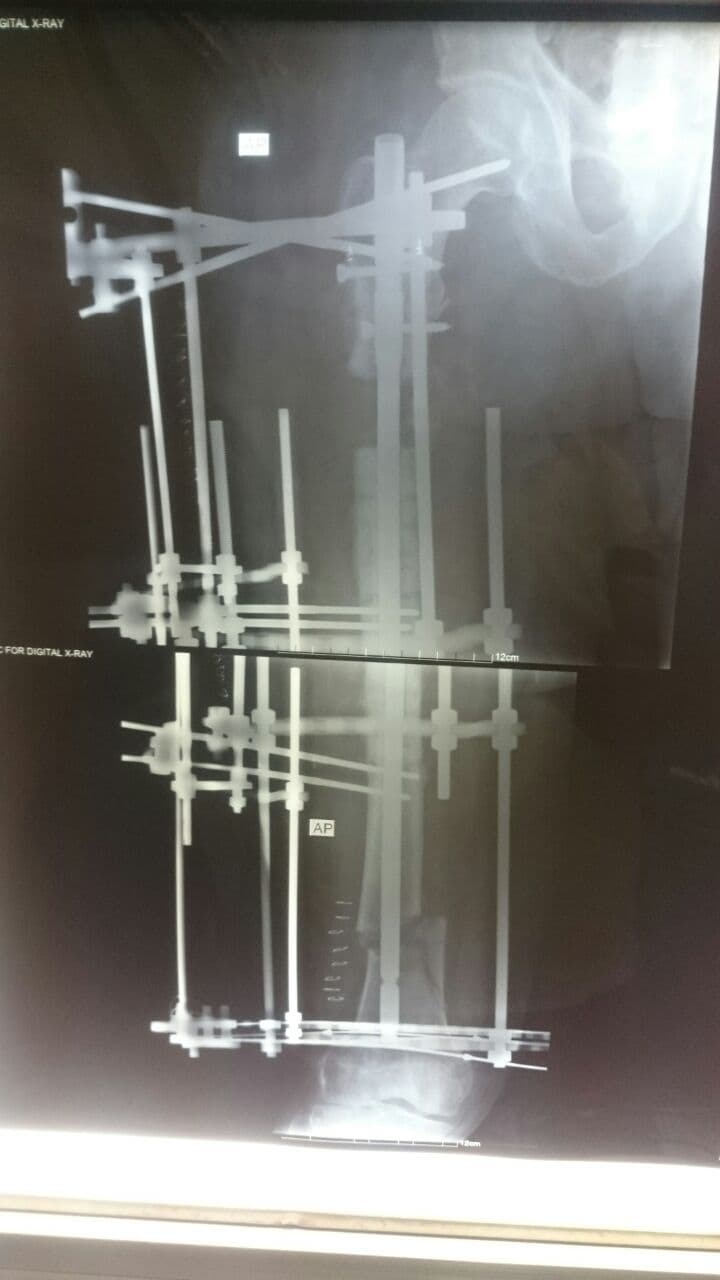

بتقنية الإليزاروف تطويل عظم الفخذ بعد فقدان (7) سم منه

أعلن فريق طبي في مستشفى الكفيل التخصصي بكربلاء نجاحه بعملية تطويل أعلى عظم الفخذ لمريض سبعيني بعد فقدان (7) سم منه.

وقال إختصاصي جراحة العظام والكسور والمفاصل بالمستشفى الدكتور محمد سعد الحارس، في حديث صحافي، إن فريقنا الطبي نجح بعملية تثبيت كسر مع تطويل العظم لفخذ مريض يبلغ من العمر (70) عاما، مبيناً إن عملية التثبيت والتطويل اُجريت بإستخدام تقنية الإليزاروف.

وأوضح الحارس، إن المريض يعاني من فقدان عظمي أعلى عظم الفخذ يبلغ (7) سم مع التهاب عظمي نتيجة عملية سابقة، مؤكداً إستعادة المريض لعافيته عقب عمليته التي اجريناها في مستشفى الكفيل.